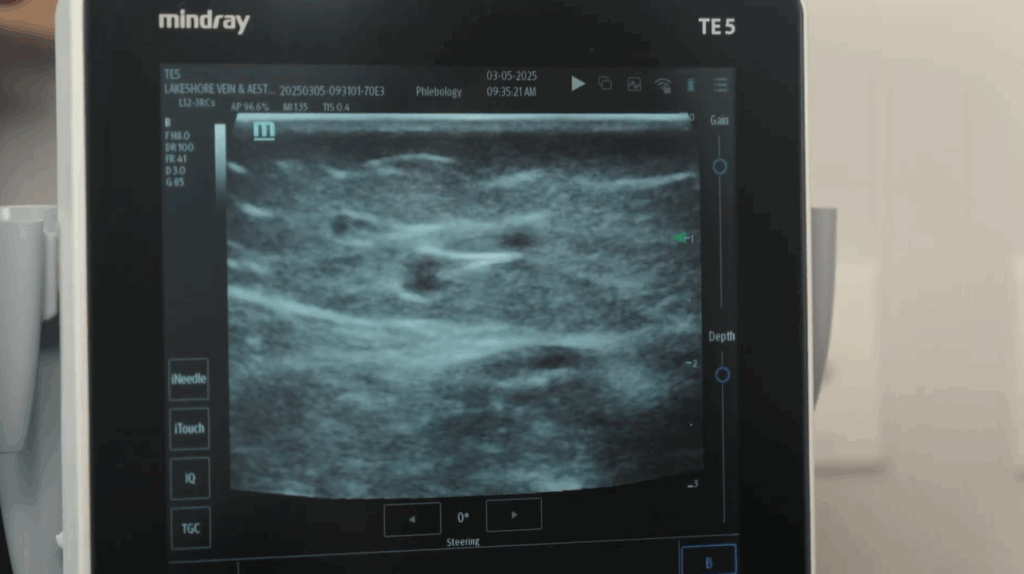

In 2025, believe it or not, the fundamentals of the human body have not changed. The underlying mechanisms remain the same, but we can diagnose these issues using ultrasound-guided vein assessments, which allow us to map exactly where valves are leaking and how severe the reflux is.

Monitoring may be reasonable if symptoms are mild, stable, and mostly cosmetic. A brief ultrasound assessment can clarify whether your veins are functioning normally or showing signs of progression.

After an ultrasound assessment, most treatments used today are minimally invasive, performed under local anesthetic, designed to close the unhealthy vein so blood can reroute into healthier ones.